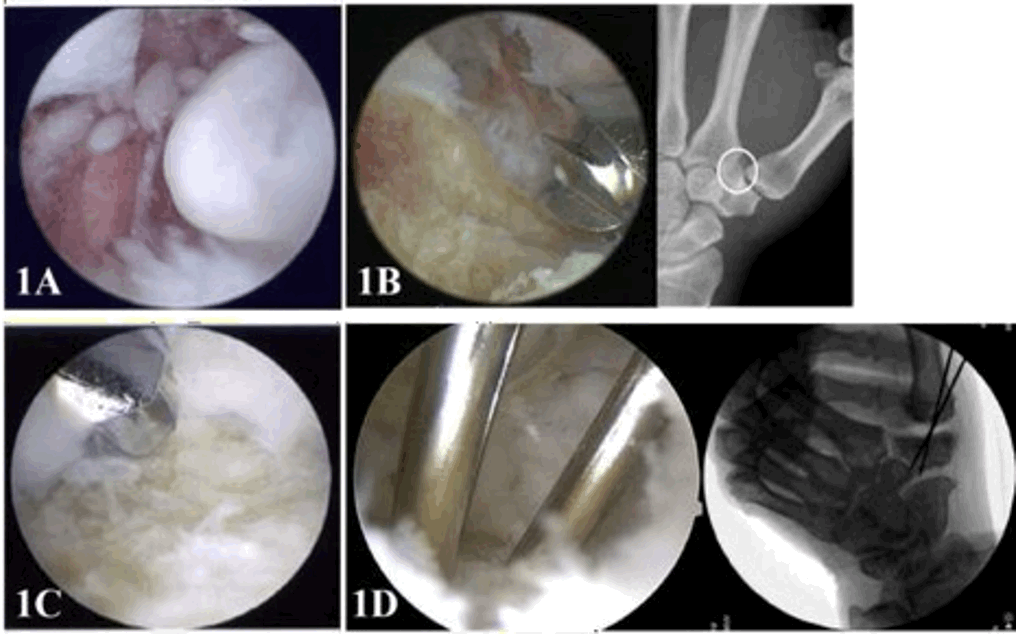

- Wrist Arthroscopic Surgery

4. Wrist Arthroscopic Surgery

5. Minimally invasive arthroscopic surgery (shoulder, elbow, wrist, hip, knee, ankle) 3D arthroscopy

d. Thumb carpometacarpal joint arthritis